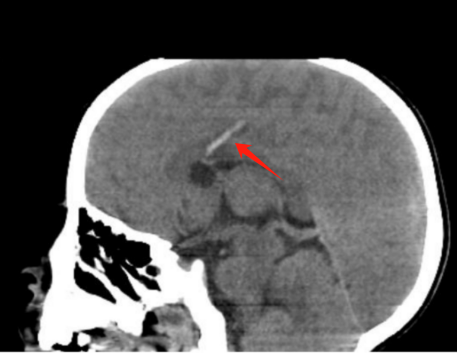

⚠️颅脑:CT:右侧脑室积气+脑实质出血;

⚠️CT片子上清晰看到:竹签自口腔,贯穿筛骨上壁,进入大脑额叶!